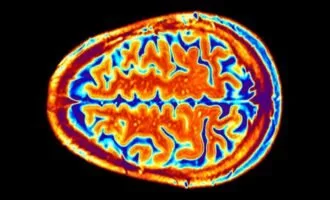

سلامت محققان: صافی سطح قشر مغز میتواند ریسک ابتلا به افسردگی را افزایش دهد

دانشمندان در پژوهشی دریافتهاند که سطح قشر مغز در افرادی که به افسردگی مبتلا شدهاند، صافتر از افراد سالم است.